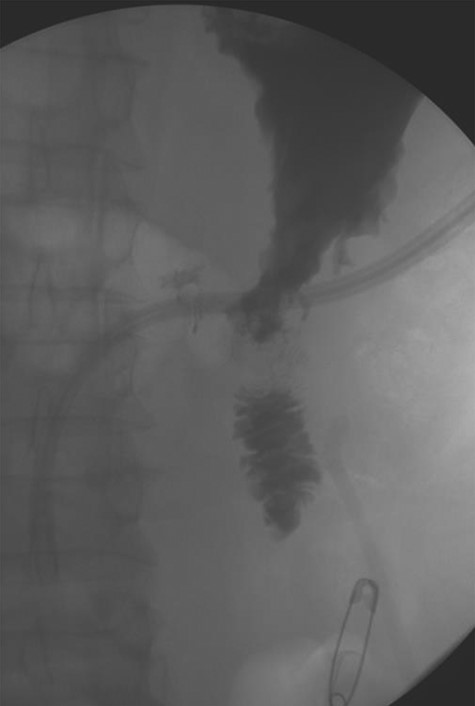

A 56-year-old African American male presented in 2015 with abdominal pain, with associated melena and hematochezia. The patient has a history of chronic back pain for which he takes 600 mg ibuprofen daily, alcohol abuse, tobacco use and a previous GI bleed in 2011, which necessitated 6 units (U) of packed red blood cells (PRBCs) and emergency therapeutic endoscopy. The patient was found to be hypotensive to 76/56 mm Hg, and hemoglobin (Hgb) was found to be 9.4 g/dl, from a previous baseline of 10.6 g/dl. His rectal examination was guaiac positive. A repeat Hgb was found to be 6.5 g/dl. The patient was given 3 U of PRBC and an emergency endoscopy was performed. On endoscopy, the patient was found to have a 6 cm gastric ulcer with an associated vessel underneath of a large clot. Due to the high risk nature of the bleed, it was felt by the gastroenterologist that the patient should undergo an endovascular angioembolization (Fig. 1). The patient was brought to the Interventional Radiology Suite for the procedure. The patient’s right common femoral artery was accessed and the celiac trunk was selected. A subselective common hepatic arteriogram was performed, which demonstrated active extravasation arising from the proximal aspect of the GDA. The GDA was then coil embolized both proximal and distal to the site of bleeding using five microcoils. Repeat arteriogram demonstrated no further opacification of the GDA and no further extravasation (Fig. 2).

Demonstrating active extravasation of the GDA during a subselective GDA arteriogram

Demonstrating coil embolization of the GDA with no opacification